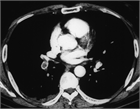

1. 呼吸不全をI型、II型呼吸不全に分類すると肺病変のみが呼吸不全の原因と思われるが、呼吸不全は複数病態の複合体である。